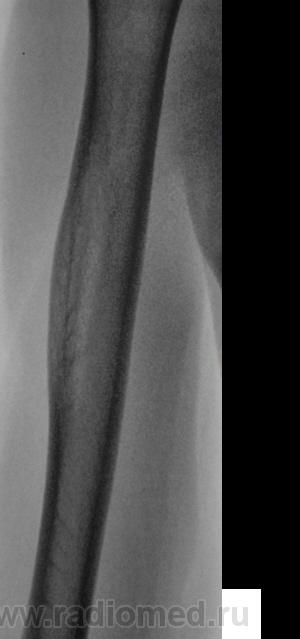

Изображения в прямой проекции с увеличением.

Мне кажется, есть локальная слоистость кортикального слоя. Надо бы спросить ту, имя которой я поклялся не упоминать.

Неоднозначно всё